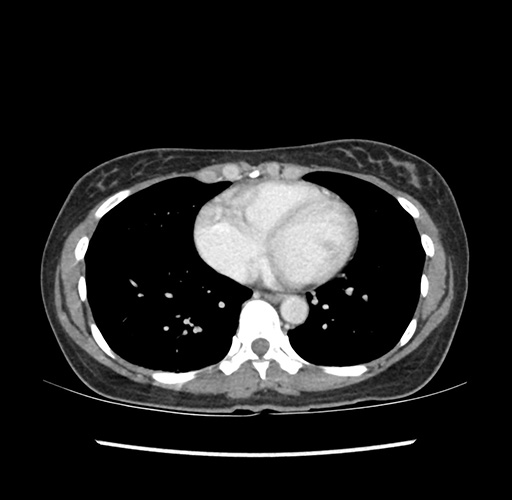

Imaging Analysis

Look through the patient's CT scan to identify any areas of concern for the necessary procedure.

Based on your CT findings, which issue(s) would give reason for "planned slowing down moment(s)" in this case?

Considering a standard left lateral sectionectomy procedure, what step(s) of the operation would you do differently in this case ?